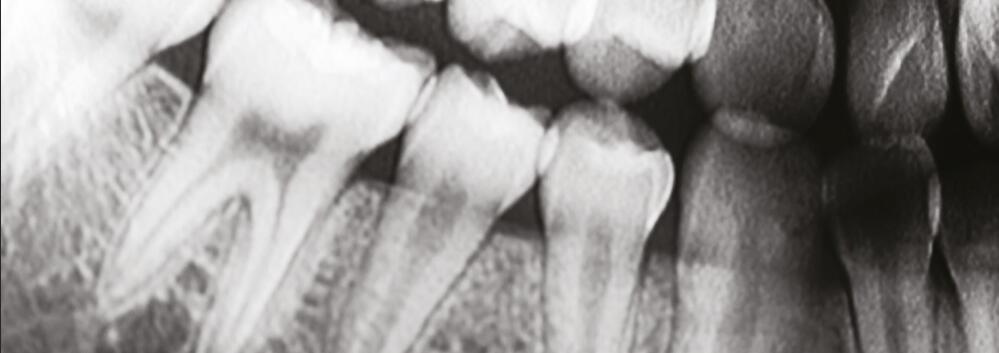

4. **圖像質(zhì)量**:使用碘化銫作為閃爍材料的X射線(xiàn)平板探測(cè)器能夠提供高分辨率和高對(duì)比度的圖像。這對(duì)于醫(yī)學(xué)成像尤其重要,因?yàn)樗梢詭椭t(yī)生更準(zhǔn)確地診斷和評(píng)估疾病。

針狀碘化銫閃爍體的掃描電鏡圖像:針狀晶體具有限光作用,能夠有效降低光的散射,進(jìn)一步提高空間分辨率